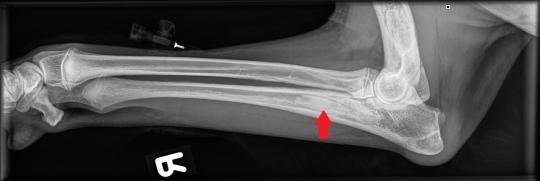

Beim Folgebesuch einige Tage später ist der Hund wieder ganz der alte - ungestüm, fröhlich und mit prächtigem Appetit gesegnet. In Sedation werden nun beide Vorderbeine geröntgt, um zu eruieren, was zu der wechselhaften Lahmheit geführt hatte.

Die typischerweise von Wachstumsstörungen betroffenen Gelenke (Ellbögen und Schultergelenke) erscheinen wie erhofft unauffällig. In sämtlichen Langknochen (Elle, Speiche, Oberarmknochen) beider Vorderbeine zeigen sich jedoch starke Veränderungen: Das Knocheninnere weist an verschiedenen Stellen fleckige Verdichtungen auf, welche die normale feine Knochenstruktur verdrängt haben. Die beobachteten Veränderungen sind typisch für eine sogenannte Panostitis. Die Besitzerin erhält einen Vorrat an Schmerzmitteln, falls das Problem wieder aufflammen sollte.